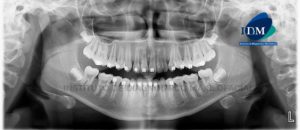

Paciente masculino de 20 años acude al Instituto de Diagnóstico Maxilofacial para evaluación imagenológica a nivel maxilofacial. A la evaluación de la radiografía panorámica se